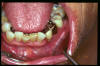

CM Edentulismo parcial, restos radiculares, caries y placa bacteriana